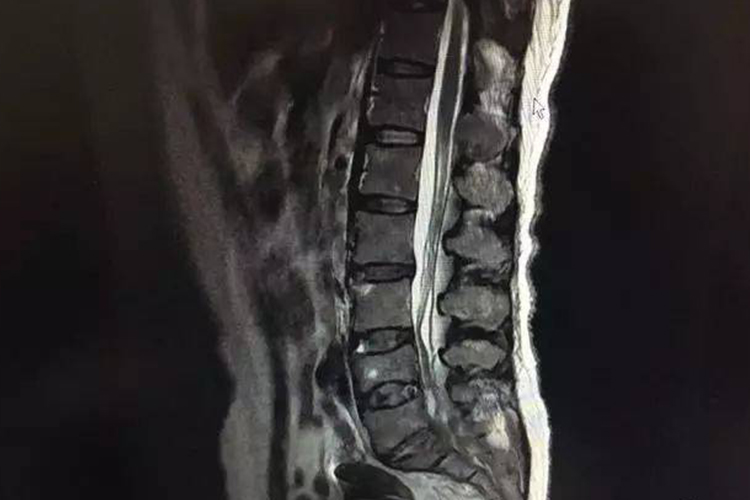

乳腺癌骨转移是晚期乳腺癌常见的并发症之一,约70%的患者会发生骨转移,特别是激素受体阳性的乳腺癌患者。四肢长骨、椎体是乳腺癌骨转移的常见部位,约占50%,其次是肋骨、骨盆、颅骨、股骨和肩胛骨等,骨转移部位主要表现为溶骨性病变。

乳腺癌骨转移后可表现为软组织肿块、肋骨软组织肿块、脊柱肿块等。骨转移可导致骨痛、病理性骨折、神经压迫症状和高钙血症等并发症,严重影响病人的生活质量,骨痛到晚期往往成为患者的主要问题。